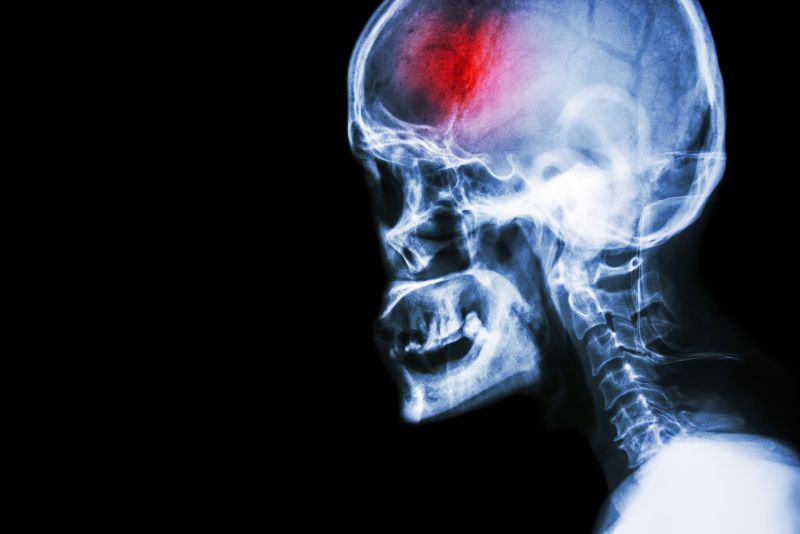

A stroke (previously known as a cerebrovascular accident) when there is a decreased flow of blood to the brain from either a blockage in the blood vessels that supply the brain (ischemic stroke), or a bleed from the blood vessels that supply the brain (hemorrhagic stroke). When the blood flow to the brain is blocked it prevents the brain from getting the needed oxygen and nutrients to function. Without oxygen the brain cells can be permanently damaged or die and the physical and mental functions related to that area of the brain will be affected. A stroke is a medical emergency and rapid treatment is crucial to decreasing the damage caused by a stroke.

- Ischemic stroke: a stroke that is caused by a blockage (clot) that disturbs the blood flow to the brain.

- Hemorrhagic stroke: a stroke that is caused by a bleed that disturbs the blood flow to the brain and puts pressure on the surrounding tissue.

When any type of stroke occurs and the blood flow to the brain is compromised, all the functions which that part of the brain controls are subsequently disturbed. The brain on one side of the head controls the movement functions and sensation on the opposite side of the body. This means that if you have a stroke on the left side of the brain, the right side of the body will be affected. If the stroke is on the right side of the brain, the left side of the body will be affected.

Every stroke is unique depending on exactly which area of the brain has been affected. The bigger the bleed or blockage and the longer that the stroke goes without treatment (to stop the bleed or unblock the blockage), the more severe the impairments and the greater number of abilities that will be affected. It is worth reiterating that time is of the essence when a stroke first occurs; early treatment can immensely improve outcomes.